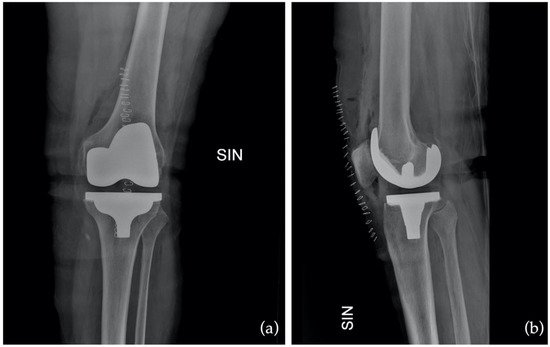

Imaging tests: You may be referred for X-rays, MRI, or CT scans to obtain a detailed view of your knee joint. These images assist in diagnosing the severity of arthritis or injury and help plan the most appropriate surgical approach.

Before your surgery, your orthopaedic team will use detailed imaging, such as X-rays and a CT scan, to develop a personalised surgical plan. These scans provide an accurate 3D map of your knee joint, helping identify its shape, alignment, areas of cartilage loss, and how arthritis has affected joint movement. This information allows Prof. Justin Hunt or Prof. Vera Maria Sallen to plan your total knee replacement procedure with a high degree of precision. Key surgical decisions, such as where to make bone cuts, how much bone to remove, and how to position your implant, are made based on your unique anatomy.

Once the joint has been prepared, the prosthetic components are positioned with a focus on restoring your natural alignment and knee movement. This step may be supported by advanced technology such as robotic-assisted systems or patient-specific instrumentation (PSI). If used, robotic or computer-assisted tools help guide the placement of the implants in real time, based on your pre-operative imaging. PSI uses 3D-printed guides tailored to your anatomy, enhancing the precision of bone cuts and implant positioning. These technologies aim to improve implant alignment, which may lead to better function and long-term outcomes. The components are secured to the bone using specialised cement or a press-fit technique, depending on your needs. Each decision is made to optimise the fit, feel, and durability of your new knee.

- Ongoing Monitoring and Support – Follow-up appointments with your orthopaedic surgeon will be scheduled to monitor your progress, assess your range of motion, and review post-operative imaging. These visits are an important part of long-term care, helping to ensure that your knee implant is functioning well and that your rehabilitation is on track.